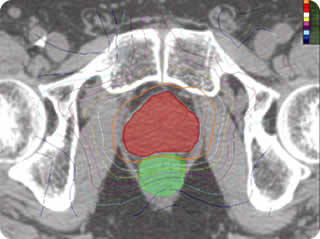

delivery. Conformal isodose curves and dose volume histograms (DVH) are used to compare

with an optimized Intensity-Modulated Radiotherapy (IMRT) plan actually delivered to the

study patient based upon CT scan-derived organ volumes. The CyberKnife can produce

superior DVHs for sparing of rectum and bladder and excellent DVHs for target coverage

compared with IMRT, and possesses dose heterogeneities to the same degree as IMRT